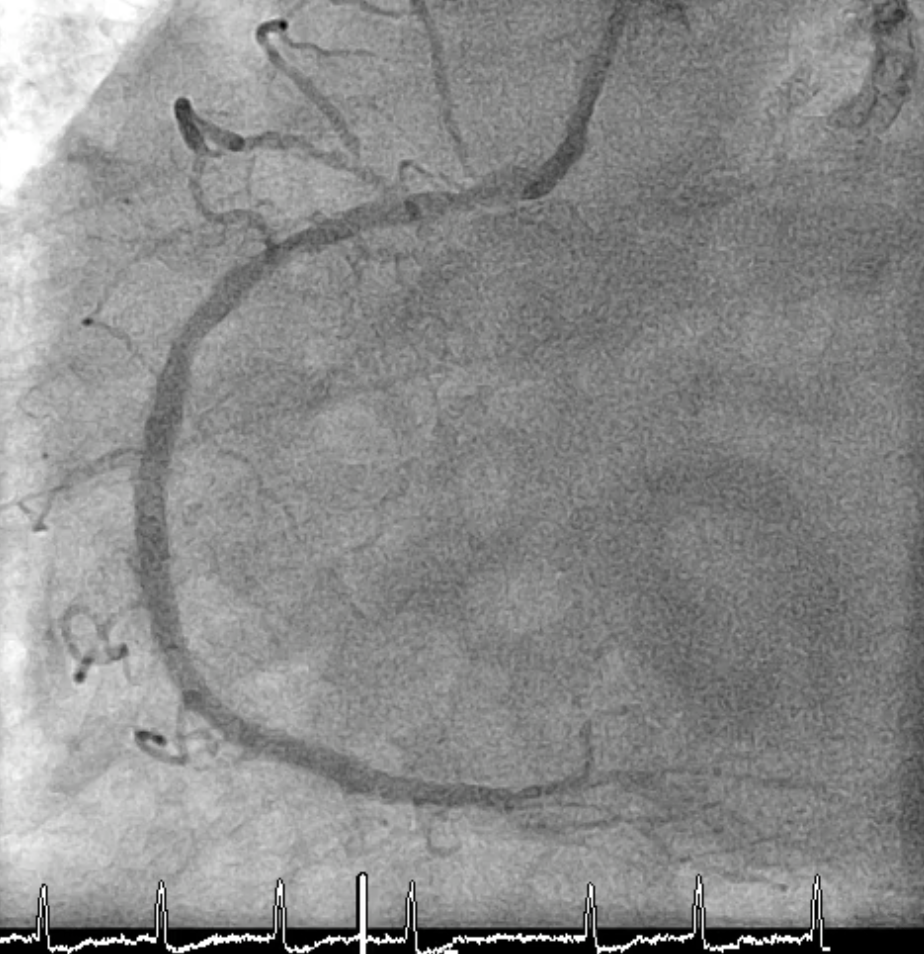

Coronary angiography revealed severe in-stent restenosis of the distal left main and bifurcation involving the LAD and LCx, with multiple overlapping stent layers. TIMI-2 flow was noted in LAD, and the LCx ostium was heavily calcified. LVEDP was 32 mmHg, and cardiac index 2.07 L/min/m©÷. The lesion was classified as a high-risk CHIP case, requiring hemodynamic support with Impella CP before complex PCI.